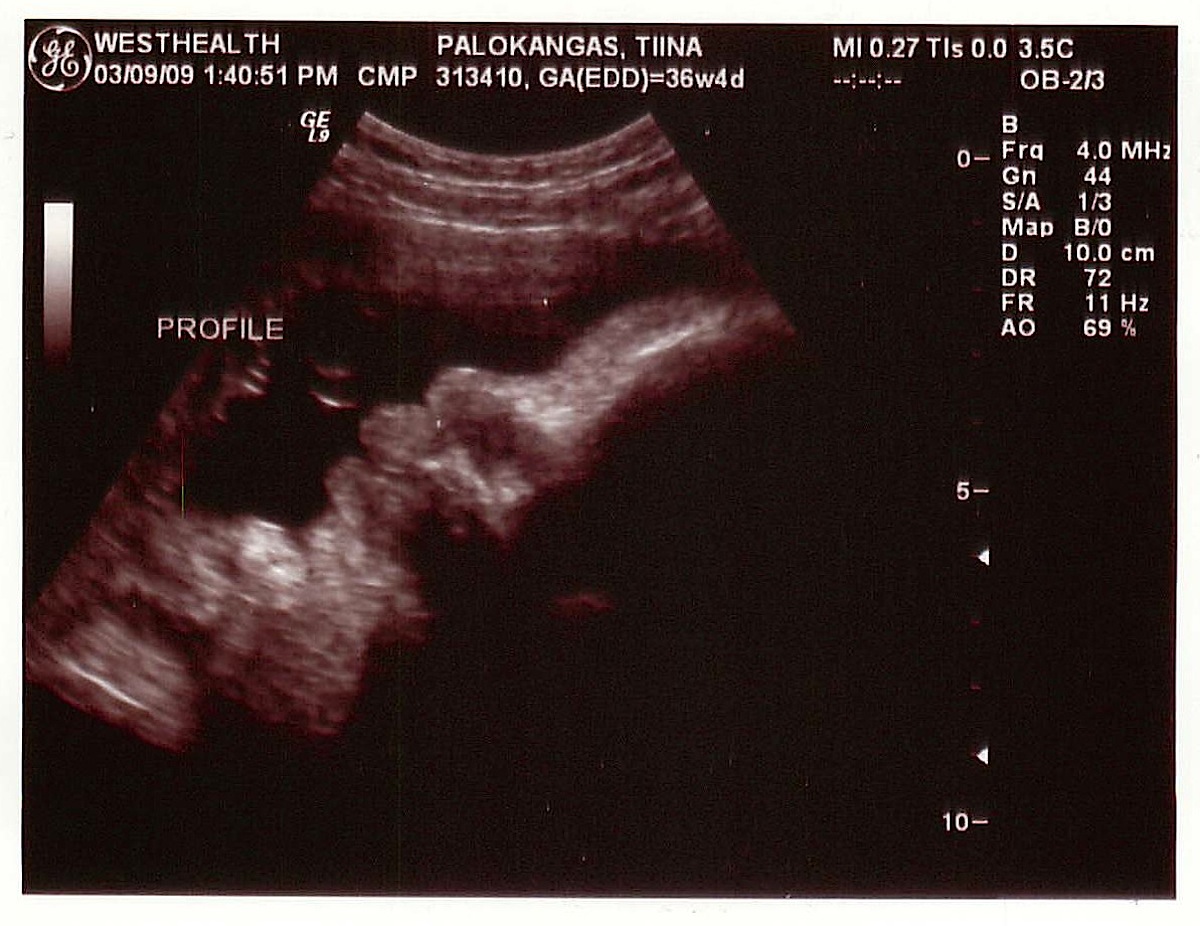

Ultrassa Eelikin erotti Masasta jo paljon enemmän kuin viime kerralla (marraskuussa). Profiili oli tuttu, melko turpeahuulinen ja nöpönenäinen. Masa oli jo tosi iso, yli kolmekiloinen (!) ja se puuhaili siellä mahassa vaikka mitä! Se haukotteli, aukoi suutaan ja massutti. Sitten se imi sormia, ensin yhtä ja sitten montaa yhtä aikaa. Sitä oli aika hauska katsella. Sitten laskettiin viisi varvasta toisesta jalasta. Toisesta ei laskettu. Eeliä alkoi Masan puuhia seuratessa mietityttää, että ”äiti, oletko sinä synnyttänyt isinkin?” Perhesuhteita käytiin läpi eilen, kun Eeli kesken välipalan syönnin yhtäkkiä kysyi äitiltä, että ”onko Veikko-pappa ja Maire-mummu sun isi ja äiti?”. Sitten me piirrettiin alkeellinen sukupuu, mitä Eeli piti tosi kiinnostavana ja katseli sitä pitkään. Isin vanhemmat piti merkitä ”Eelin mummuksi ja Eelin papaksi”.

”Digi-Masa” näyttää kuvissa kauniilta.

having seen her face and feet in reality – these ultrasound shots are amazingly accurate!